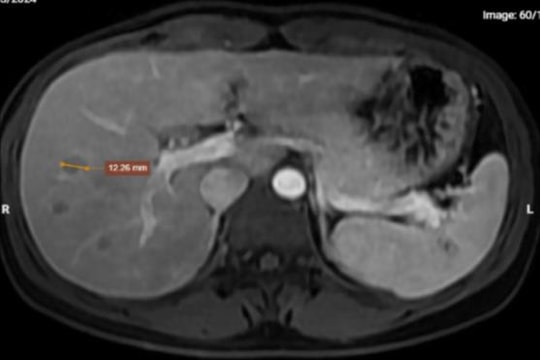

Sau khi thăm khám lâm sàng và soi mắt dưới kính hiển vi, các bác sĩ phát hiện một ký sinh trùng trong suốt, hình dạng giống giun chỉ, có kích dài, đường kính 0,5mm đang chuyển động tại vùng thái dương dưới kết mạc nhãn cầu.

Nhận định đây là một ký sinh trùng giun trưởng thành, các bác sĩ khoa Mắt đã tiến hành phẫu thuật khẩn cấp và gắp được nguyên con giun dài 14cm ra khỏi kết mạc mắt của bệnh nhân. Đây là một trong số những ca bệnh rất hiếm gặp trong lĩnh vực nhãn khoa.